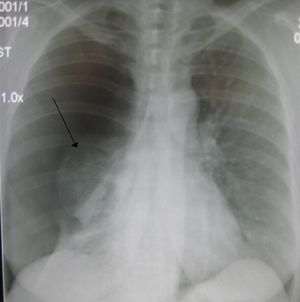

| Right sided spontaneous pneumothorax. An arrow indicating the edge of the collapsed lung. | |

استرواح الصدر هواء أو غاز في التجويف الغشائي الجنبي بين الرئتين وبين جدار الصدر، حيث يوجد غشاء رقيق، متصل يغطي الرئتين من الخارج، كما يبطن جدار الصدر من الداخل، يُسمى غشاء الجنب أو البلورا. انظر: غشاء الجنب. ومن الطبيعي أن يكون جزء البلورا المغطي للرئتين مجاوراً للجزء الموجود على الجانب الداخلي من الصدر لايفصل بينهما سوى خيط رفيع من السائل. ولاوجود للهواء عادة في هذا التجويف القائم بينهما. فإذا حدث ودخل هواء أو غاز في تجويف البلورا، فإنه يدفع بقسمي الغشاء للابتعاد بعضهما عن بعض. فإذا تجمّع قدر كبير من الهواء أو الغاز بين قسمي البلورا على جانب من الصدر، فإن الرئة لاتستطيع أن تتمدد بحرية كاملة في هذا الجانب، ومن ثم يصبح التنفس صعبًا، بل وربما تتعرّض الرئة لحالة هبوط رئوي.

وقد يحدث استرواح الصدر نتيجة جرح في الصدر بفعل سكين أو طلقة رصاص أو نتيجة حدوث تمزق مفاجىء في الرئة. كذلك فإن عدوى تجويف البلورا عن طريق الجراثيم المنتجة للغازات يمكن أن تسبب استرواح الصدر. وفي هذه الحالة يقوم الأطباء بإزالة الغاز عن طريق الامتصاص لعلاج استرواح الصدر، وجراحياً بتضميد الصدر، أو الرئة، أو بوصف بعض المضادات الحيوية في حالة وجود العدوى.